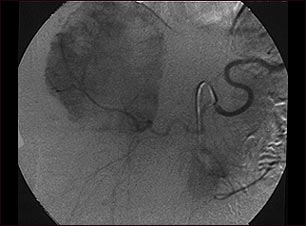

Angiograma de hemangioma

Este angiograma (una radiografía tomada después de inyectar un medio de contraste en el torrente sanguíneo) muestra una masa de vasos sanguíneos (hemangioma) en el hígado.